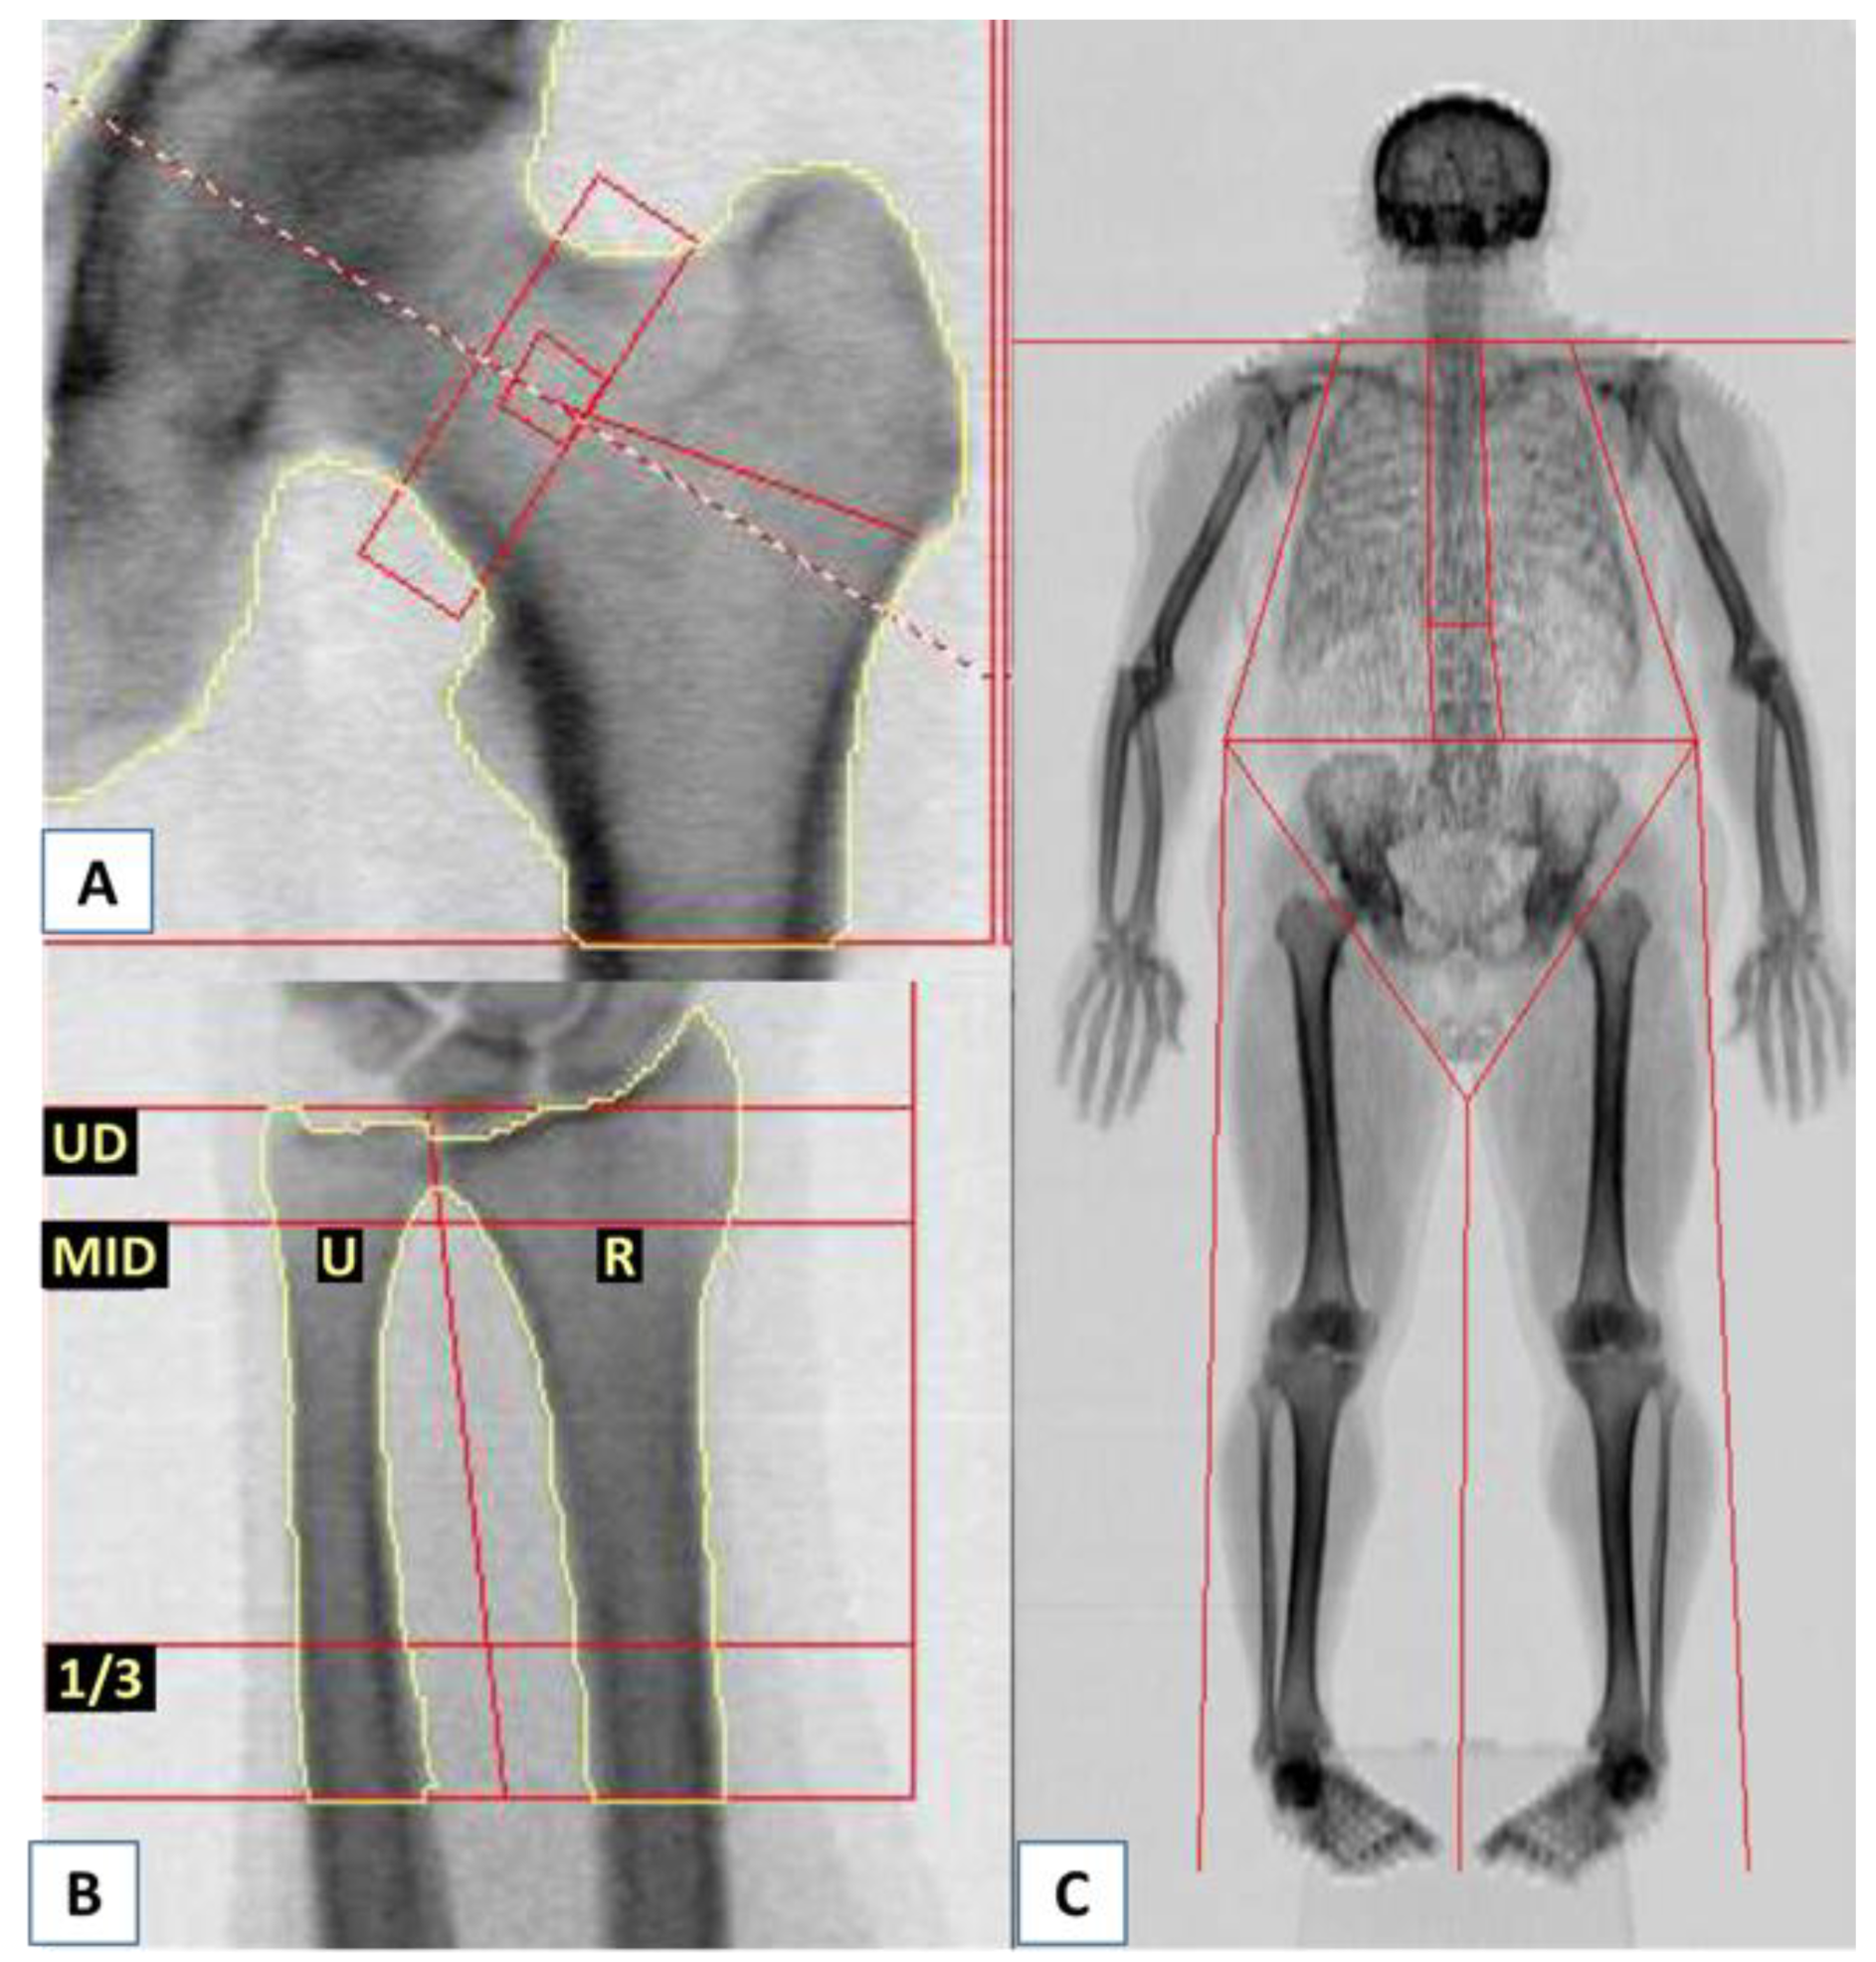

| (A). Lumbar Spine BMD Results Assessed by DXA. | |||||||

|---|---|---|---|---|---|---|---|

| Region | Area cm2 | BMC g | BMD g/cm2 | T-Score | PR% | Z-Score | AM % |

| L1 | 15.42 | 12.20 | 0.791 | −2.6 | 74 | −2.1 | 77 |

| L2 | 16.95 | 13.26 | 0.782 | −2.8 | 71 | −2.4 | 75 |

| L3 | 18.40 | 15.09 | 0.820 | −2.6 | 74 | −2.1 | 78 |

| L4 | 22.48 | 22.16 | 0.986 | −0.9 | 90 | −0.4 | 95 |

| L1–L4 | 73.26 | 62.70 | 0.856 | −2.1 | 78 | −1.7 | 82 |

| (B). TBS Results in Relation to Lumbar Spine BMD. | |||||||

| Region | TBS | TBS T-Score | TBS Z-Score | BMD g/cm2 | |||

| L1 | 1.067 | - | - | 0.791 | |||

| L2 | 1.186 | - | - | 0.782 | |||

| L3 | 1.189 | - | - | 0.820 | |||

| L4 | 1.316 | - | - | 0.986 | |||

| L1–L4 | 1.190 | −2.4 | −1.4 | 0.856 | |||

| L1–L3 | 1.147 | −2.6 | −1.6 | 0.798 | |||

| L1–L2 | 1.127 | −2.3 | −1.4 | 0.786 | |||

| L2–L3 | 1.187 | −2.7 | −1.7 | 0.802 | |||

| L2–L4 | 1.230 | −2.5 | −1.4 | 0.873 | |||

| L3–L4 | 1.252 | −2.5 | −1.5 | 0.911 | |||

| (C). BMD Results Assessed by DXA at other Sites (Femoral Neck, Forearm, and Total Body). | |||||||

| Femoral neck | 6.33 | 5.87 | 0.927 | +0.0 | 100 | +0.8 | 114 |

| Ultradistal part of non-dominant (left) forearm; radius and ulna | 7.57 | 3.79 | 0.500 | −0.2 | 98 | +0.5 | 106 |

| 1/3 Distal part of non-dominant (left) forearm; radius and ulna | 6.28 | 4.79 | 0.762 | −1.1 | 92 | −0.5 | 96 |

| Total body | 2330.89 | 2502.36 | 1.074 | −1.3 | 90 | −1.0 | 91 |